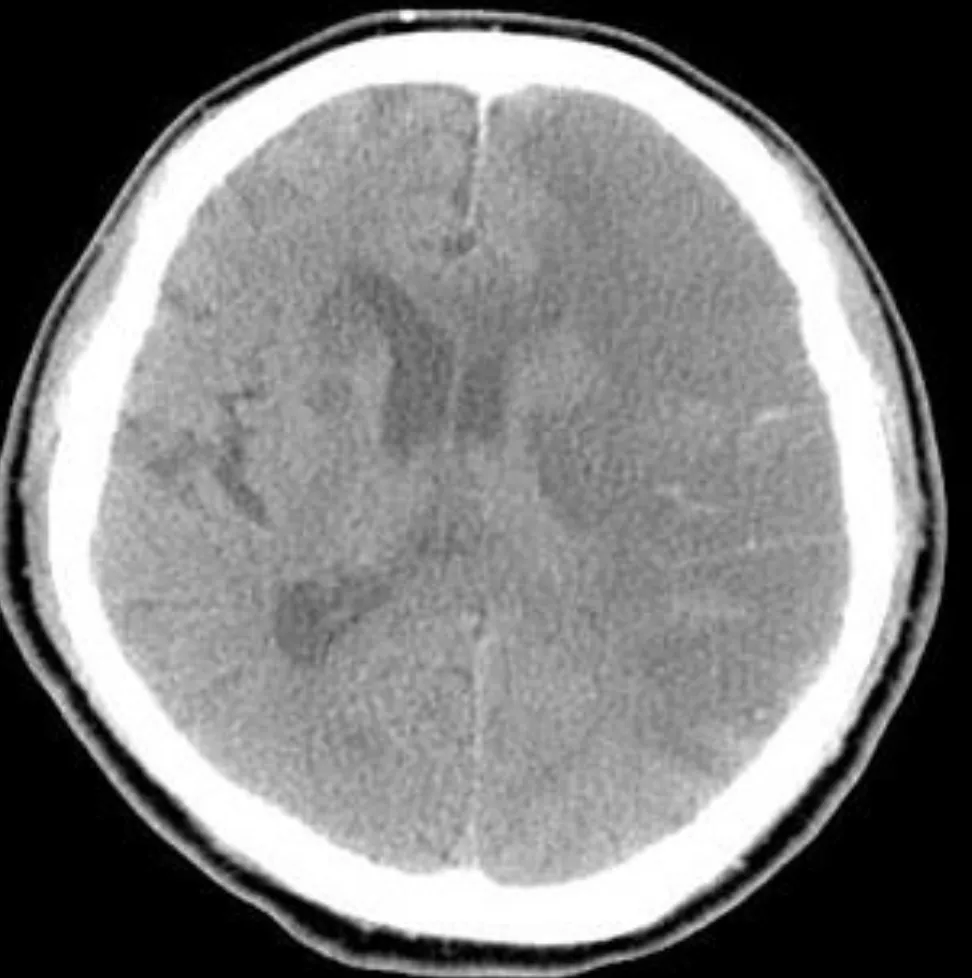

這題的解題核心在於辨識腦部電腦斷層影像顯示的是急性腦出血,並了解不同降腦壓治療方式的適用時機,特別是類固醇在急性腦出血中的角色。圖片中右側大片亮白色區域就是急性出血。